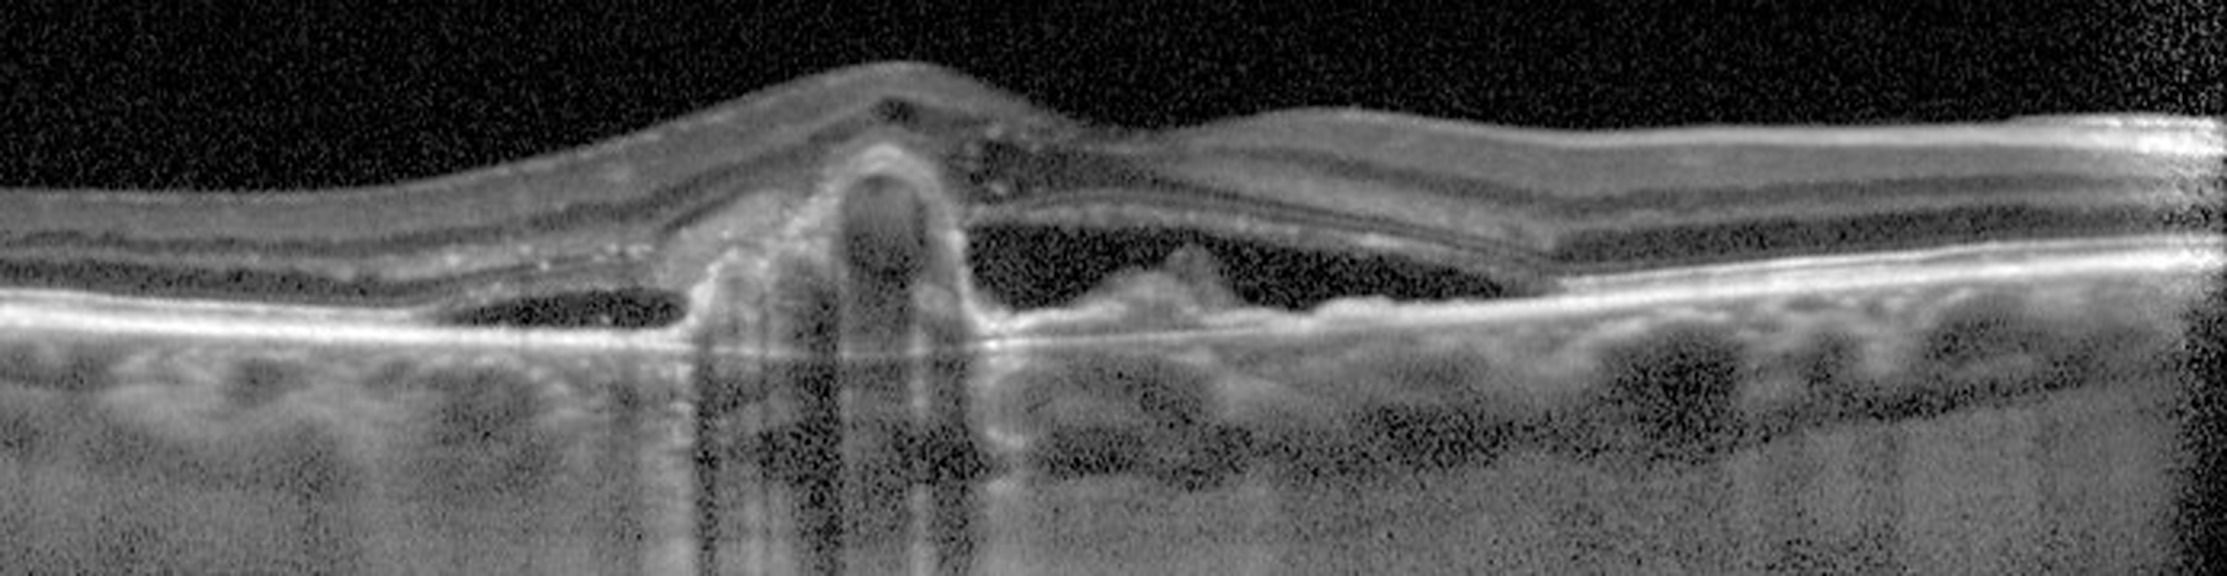

La vasculopathie polypoïdale choroïdienne (VPC)  est décrite comme une vascularisation anormale et ramifiée de la choroïdienne interne, associée à des dilatations vasculaires anévrismales pouvant être responsable de décollement de l’épithélium pigmentaire séreux et parfois d’un véritable tableau hémorragique. Si la VPC est le plus souvent idiopathique, elle peut également être secondaire à une DMLA exsudative. Il est donc important de reconnaître une VPC et de la différencier d'une DMLA exsudative pour adapter au mieux la prise en charge de son patient.